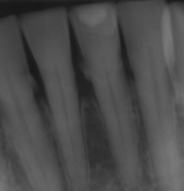

first radiographic sign of furcation involvement

pdl widening at furcation

circumferential bone loss

known as cratering in a localized area around the tooth, indicating periodontal disease.

bone loss with furcation involvment